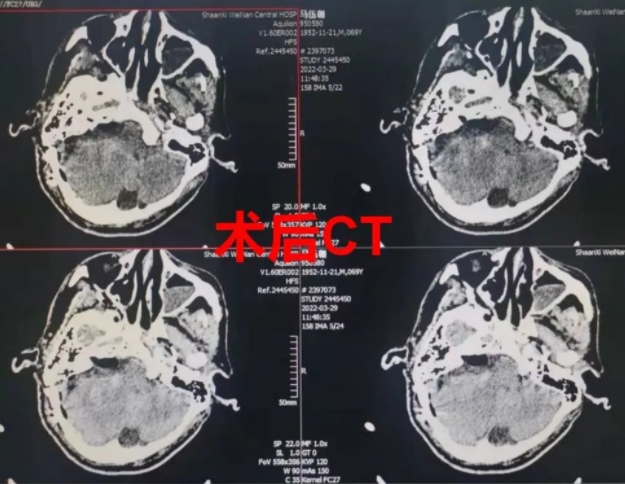

3月28日,由主任医师赵金安监台,主治医师段吉强主刀,历时8小时顺利完成手术,术中肿瘤全切、各神经血管完整解剖保留,术中出血约200ml。术后1小时患者即苏醒,生命体征平稳。